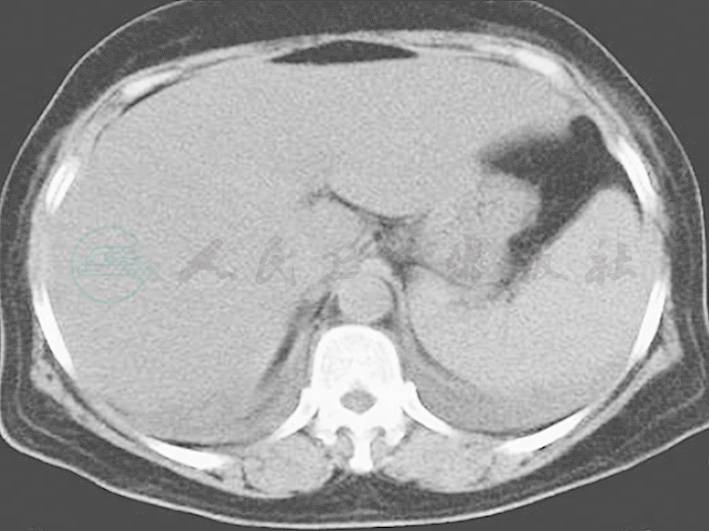

图1 胸腹部CT

两肺纹理增多增粗,两下肺背侧见斑片高密度影,边界模糊;两侧少量胸腔积液(7月8日)